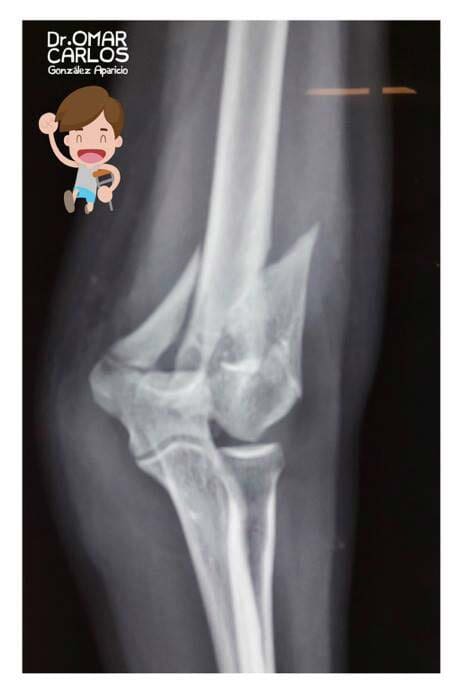

b) Lesiones fisarias: relevantes por el potencial desarrollo de secuelas en el patrón de crecimiento de la extremidad afectada; los reportes indican hasta 27 % de incidencia.